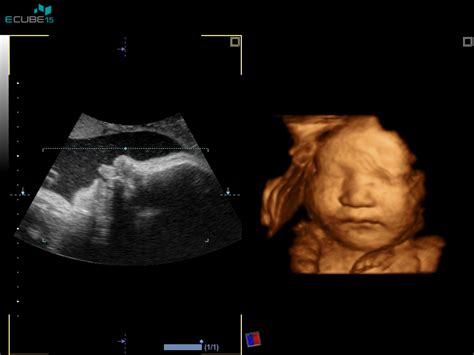

V tem ključnem tednu nosečnosti se nadaljujejo pomembni razvojni procesi ploda. Ključni razvoj se dogaja na področju čutil, predvsem vida. Ne glede na to, kakšne barve bodo na koncu postale oči vašega otroka, se oči že odzivajo na svetlobo in zenice se že lahko razširijo in skrčijo. To pomeni, da otrok že dojemajo svetlobo, ki prodira skozi materničino steno. Otrokove veke so že dobro razvite, tako da lahko po želji odpira in zapira oči. Barva oči vašega otroka je v veliki meri odvisna od genetike. Nič takega ni, kar bi lahko naredili ali pojedli v nosečnosti ali po rojstvu otroka, da bi se barva spremenila. Če imata oba s partnerjem enako barvo oči, obstaja velika verjetnost, da bo imel enako barvo oči tudi vajin otrok, a to ni povsem gotovo, saj je dedovanje barve oči kompleksno.

Otrok se zdaj premika občutno manj. Deloma zato, ker v maternici za to ni več dovolj prostora, deloma pa tudi zato, ker ima zdaj že ustaljen ritem spanja in budnosti. Spi lahko tudi več kot 15 ur na dan. Ko je buden, pa lahko vsekakor pošteno občutite vse, kar počne. Njegovi udarci in brce v telesne organe so včasih zelo močni in lahko povzročijo tudi manjše težave. Otrok se zaenkrat sicer še ni premaknil v položaj, v katerem bo ob rojstvu, bo pa postopoma ležal čedalje bližje steni maternice. Njegova glava se bo začela premikati proti mestu, kjer mora biti, ko bo prišel čas, da otrok skozi porodni kanal zapusti maternico. Še pred začetkom popadkov in poroda mora biti otrok v pravem položaju, kar pomeni, da je z glavo obrnjen navzdol proti materničnemu vratu. Babica bo od sedaj naprej redno preverjala otrokov položaj.